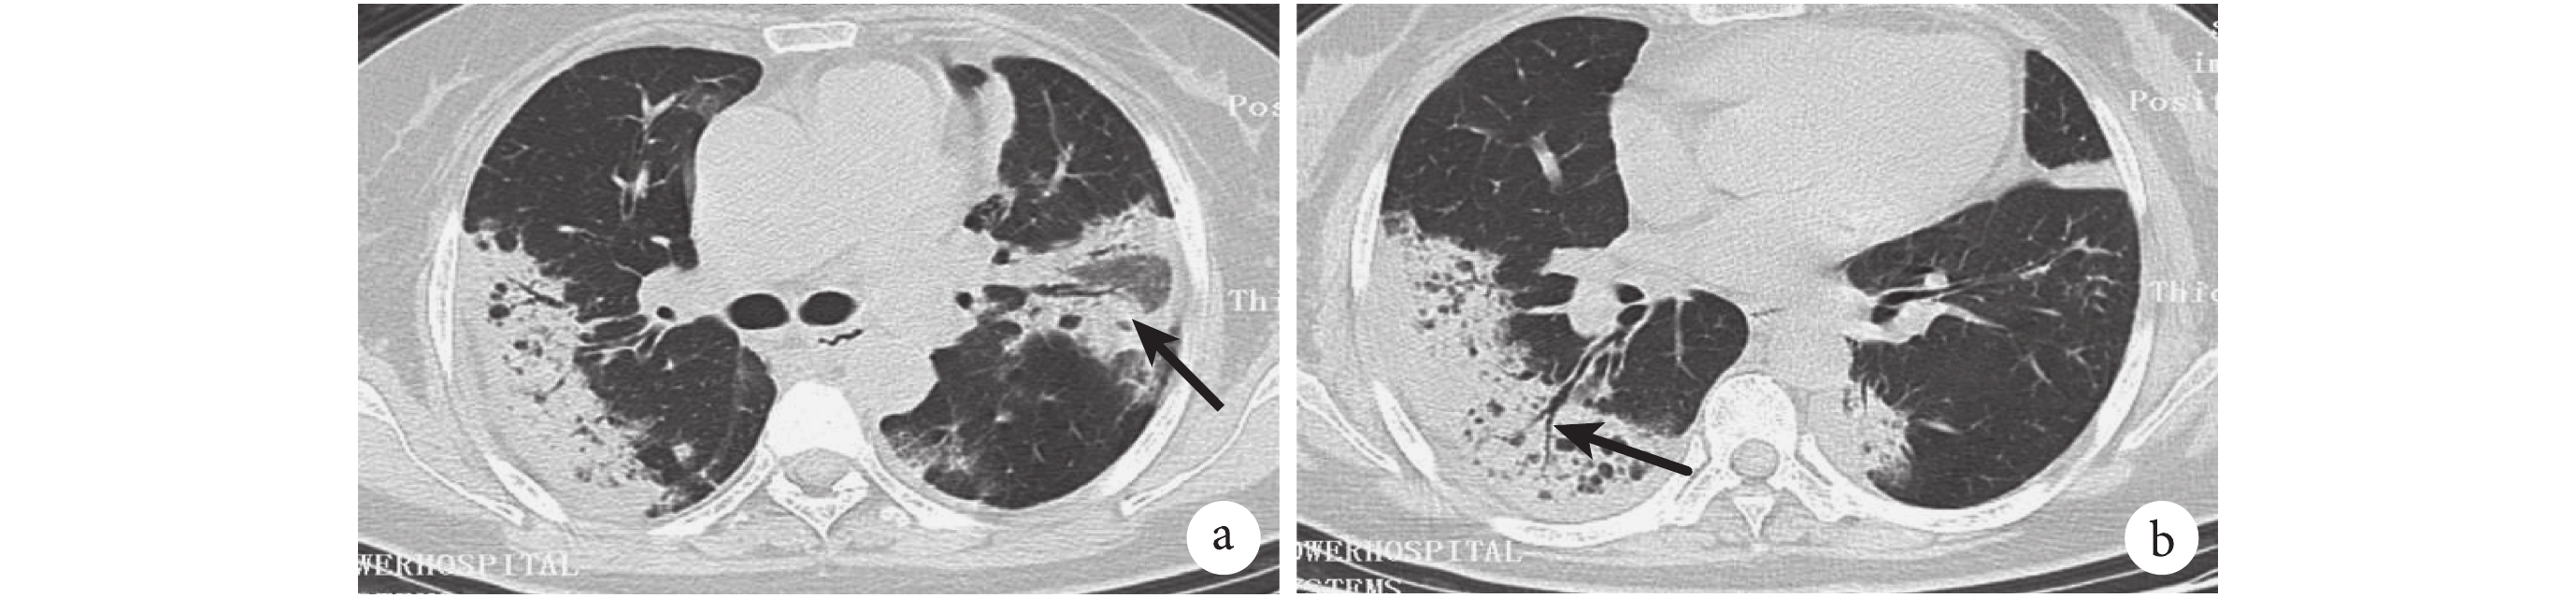

患者,女,65 歲,CT 引導下經皮肺穿刺活檢病理示機化性肺炎改變,結合臨床及影像學表現診斷為 COP。a. 雙側胸膜下分布實變影,左肺見反暈征(黑箭);b. 右肺見走形完整的 EABG,伴有牽拉性支氣管擴張改變(黑箭)

圖 1~4 展示了 2 例 CAP 及 2 例 OP 患者的胸部 HRCT 影像學特征。在實變影的分布上,69.6% 的 OP 患者呈雙側分布,顯著高于 CAP 組的 30.3%(χ2=22.412,P=0.000)。分別有 41.4% 和 16.1% 的 OP 患者實變影呈胸膜下(圖 1)、支氣管血管周圍(圖 2)分布,在 CAP 組分別為 19.2% 和 1.0%,差異有統計學意義(χ2=8.886,P=0.003;P=0.000)。87.5% 的 OP 患者胸部 HRCT 上有數量不等、形態各異的 ABG,顯著高于 CAP 組的 72.7%(χ2=4.558,P=0.033)。OP 患者的 ABG 數量的中位數及四分位數間距為 4(2~8),顯著高于 CAP 組的數量 2(0~4)(z=3.640,P=0.000)。在形態上,58.9% 的 OP 患者存在 EABG(圖 1b、圖 2a),顯著高于 CAP 組的 21.2%(χ2=22.413,P=0.000)。26.3% 的 CAP 患者有斷續 ABG(圖 3、圖 4),16.1% 的 OP 患者有斷續 ABG(圖 2b),差異無統計學意義(χ2=2.125,P=0.148)。

間質性肺炎的其他征象如牽拉性支氣管擴張(圖 1b、圖 2a)、磨玻璃影(ground glass opacity,GGO)在 OP 患者中更多見,分別為 26.8% 和 39.3%,而在 CAP 組僅為 1.0% 和 11.1%。1.0% 的 CAP 患者有反暈征,顯著低于 OP 組的 26.8%(圖 1a、圖 2a)(χ2=25.671,P=0.000)。胸腔積液(圖 3)和支氣管壁增厚(圖 4b)在 CAP 患者中更常見,為 56.6% 和 35.4%。其他影像學特征詳見表 3。